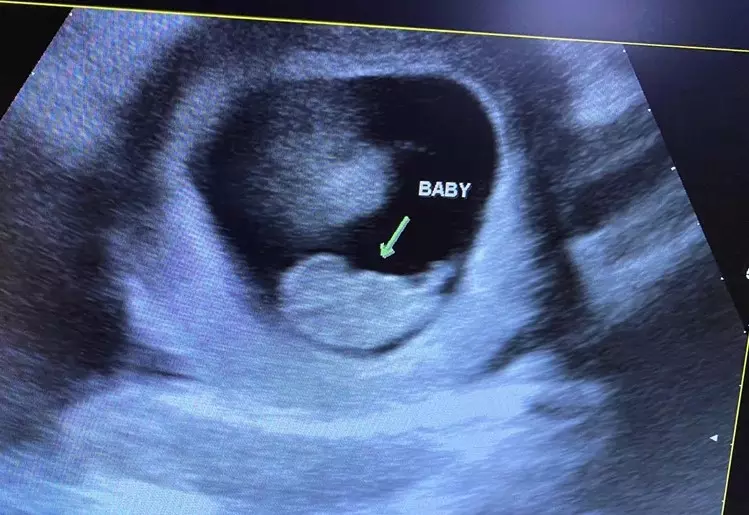

Heartbeat of Miami operates four pregnancy resource medical clinics in Miami-Dade County, with a sonographer working at each facility. Jashley visited the North Miami center, and during her appointment, she and her boyfriend were able to see their six-week-old unborn child on the ultrasound. They also heard their little one’s heartbeat. These experiences caused them to change their minds about abortion.

Later, when Jashley was 24 weeks along, she returned to the clinic for a 3D/4D ultrasound, which revealed a baby girl. Jashley’s child is due in April, Avila said.